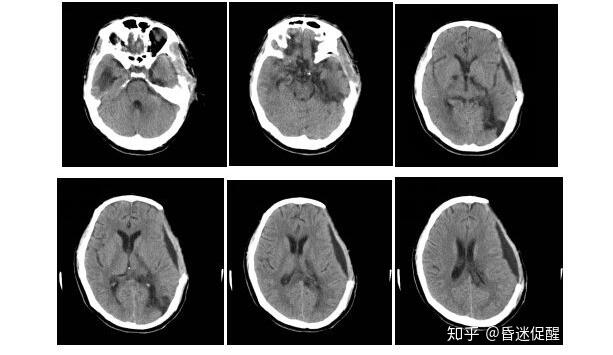

术后1个月(2017-06-26)